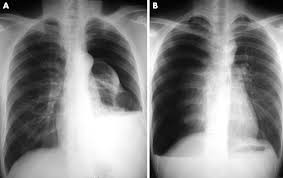

The direct contact between air and water results in a flat interface (arrows) rather than the characteristic 'meniscus' shape of a simple pleural effusion. Tap on/off image to show/hide findings. Distracting injuries such as fractures or peritonitis were also noted. On an expiration film, the pneumothorax will be more evident because on expiration, there is less lung air, therefore, the lungs will look whiter, making the density difference between the pneumothorax and the lungs more evident, and the size of the pneumothorax will appear larger. Patients with tension pneumothorax usually appear dyspnic and distressed. 6 10 supportive findings of pneumothorax. An occult pneumothorax refers to one missed on initial imaging, usually a supine /semierect chest radiograph 24. Patients will not always be symptomatic and treatment will depend on the cause.

The condition spans all age groups, and ems providers should, therefore, maintain a high index of suspicion for pneumothorax for any patient with a. Tap on/off image to show/hide findings. However, treatment is reliant on timely review of radiographs. If you cannot diagnose a tension pneumothorax at medical finals you won't find an examiner who will defend you. A normal or raised paco 2 is concerning as it indicates that the patient is tiring and failing to ventilate effectively. Ipsilateral pleural line with reduc ed/absent lung markings (i.e., increased transparency) abrupt change in radiolucency; Pneumothoraces may be small or very large. In this video, you'll learn how to identify when radiological pleura is abnormal and the key signs to look out for when trying to diagnose a pneumothorax.

Finding of pneumothorax on chest radiographs may include the following: The condition spans all age groups, and ems providers should, therefore, maintain a high index of suspicion for pneumothorax for any patient with a. Pneumothorax describes gas within the pleural space. Hover on/off image to show/hide findings. Clinical signs of a tension pneumothorax in the ventilated patient are comparably rapid, with arterial and mixed venous peripheral capillary oxygen saturation immediately decreasing 5.

Hover on/off image to show/hide findings. Finding of pneumothorax on chest radiographs may include the following: Typical abg findings in pneumothorax include low pao 2 and low paco 2 (due to hyperventilation). A pneumothorax refers to the presence of gas or air in the pleural space. This may occur because of a number of reasons and may be spontaneous. The video is an effort to revisit the pneumothorax. Pneumothorax describes gas within the pleural space. Schematic illustration of the radiographic findings and differences between pneumothorax and artifacts related to skinfolds.